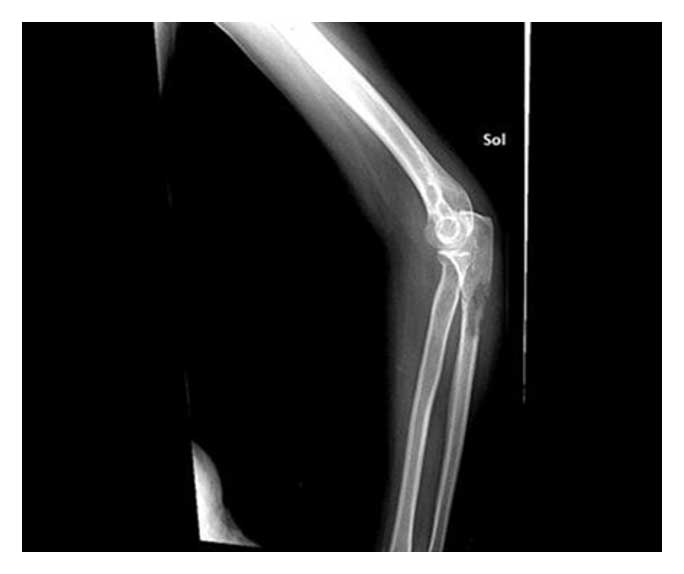

Ameliyat Öncesi: Röngende proksimal ulnada yeniklik ve kırık riski görülmekte.